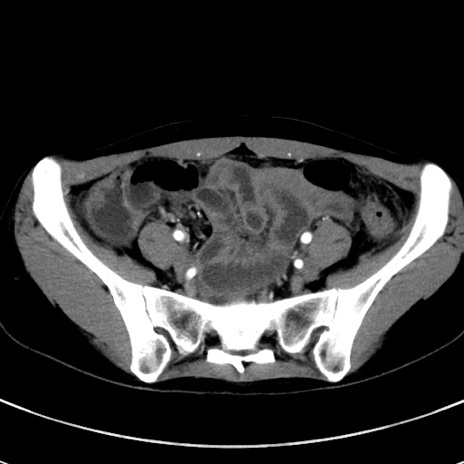

症例17(横断像)

【症例】20歳代女性

【主訴】嘔吐、下腹部痛

【現病歴】昨日夕食後に嘔吐し下腹部痛が出現。本日になっても嘔吐持続し改善しないため来院。

【身体所見】意識清明、BT 37.2℃、BP 108/67mmHg、腹部:平坦、やや硬、下腹部正中から右にかけて圧痛あり、反跳痛軽度あり、tapping pain(+)。

【データ】WBC 13600、CRP 14.94